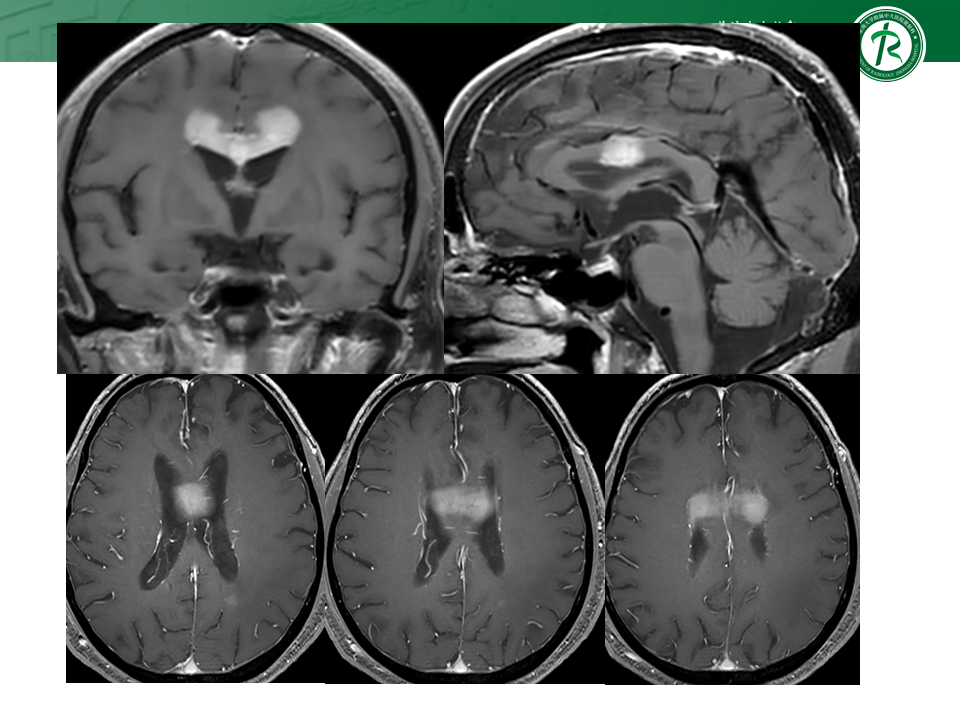

跨中线的脑内占位的影像分析思路